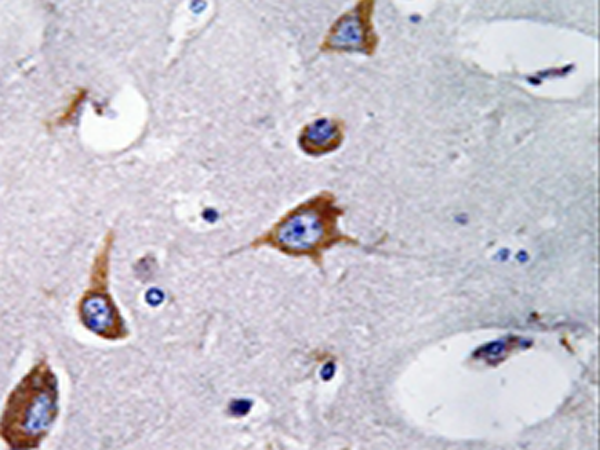

IHC positive control: |

Human brain tissue |